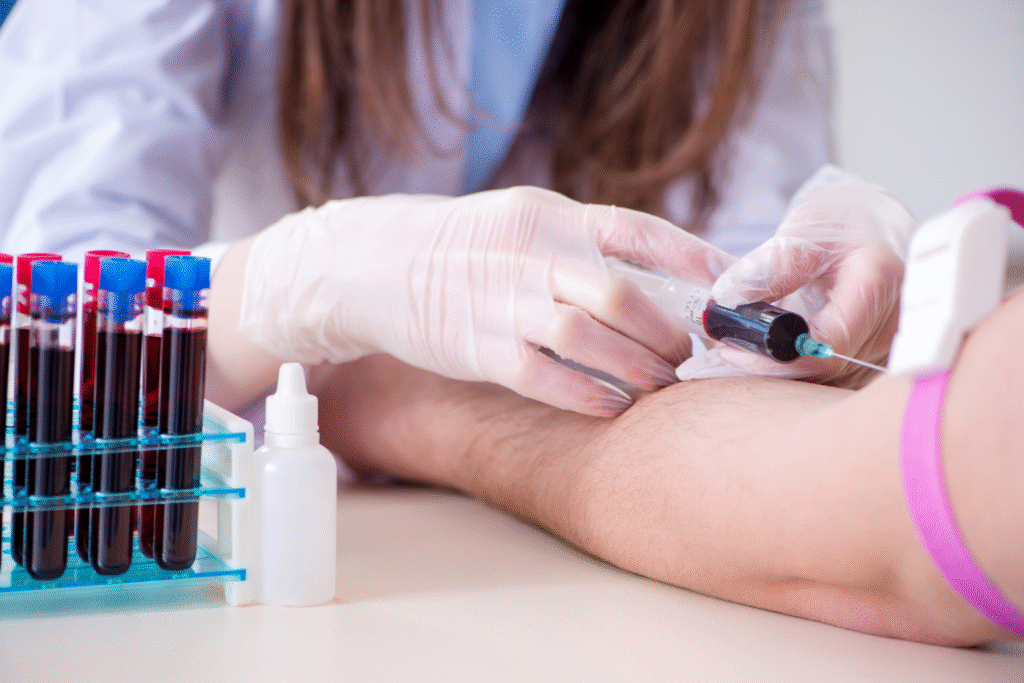

5. A CtBP2 blood test might eventually reveal your true biological age.

Since CtBP2 levels correlate with healthy lifespan and decreased levels with frailty, a blood test measuring its concentration could estimate your “biological age” — how your body is really doing compared to your years. That matters because two people aged 65 might biologically be 55 and 75, respectively, based on health, lifestyle and genetics. A CtBP2 assay would give tangible feedback rather than general advice.

With that information you could personalize lifestyle, medical and nutritional interventions—not just for disease prevention but aging management. It’s shift from reactive healthcare to proactive optimization.

9. Your longevity strategy may now include tracking key biomolecules, not just behaviours.

With the CtBP2 discovery, aging isn’t only a matter of eating right and exercising—it’s measurable, trackable and potentially tuneable. You may soon ask your doctor: “What’s my CtBP2 level?” alongside “What’s my cholesterol?” It adds depth to health management.

That doesn’t mean you abandon fundamentals—sleep, nutrition, activity still matter—but now you might pair them with biomarker monitoring. It’s aging with feedback, not guesswork.